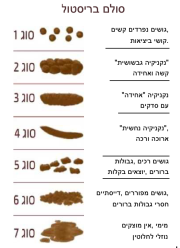

| 20:20, 27 בינואר 2024 | סולם בריסטול.png (קובץ) |  |

178 קילו־בייטים | Roeitul | 1 | |